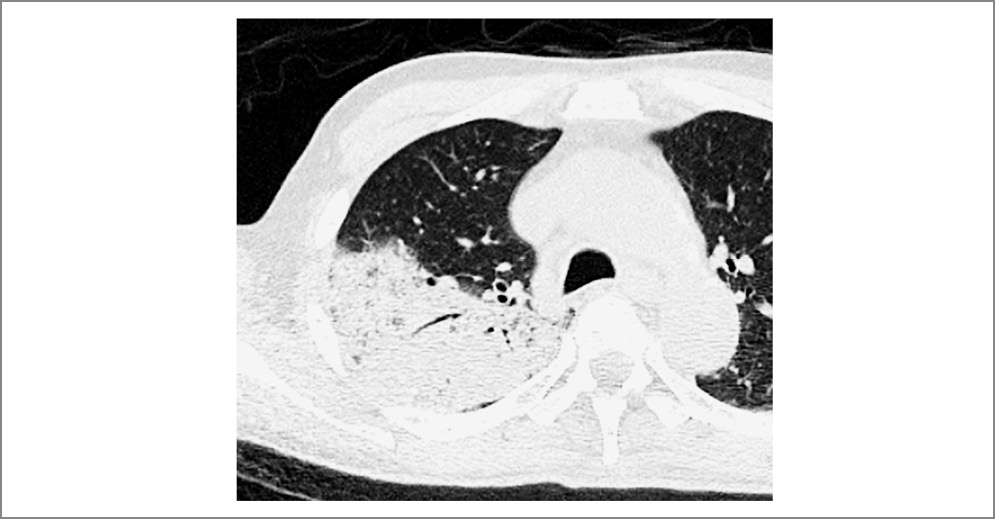

Для бактериального поражения легких характерны такие признаки на рентгенографии ОГК, как очаг(и) инфильтрации легочной ткани (понижение прозрачности), рис. 1; нечеткие контуры уплотненного участка (за исключением мест соприкосновения с междолевой плеврой); видимость воздушных просветов бронхов в уплотненном участке. Очень часто рентгенологи описывают усиление сосудистого рисунка и бронхов как признак пневмонии, что ведет к гипердиагностике и необоснованному назначению антибактериальных препаратов.

Рис. 1. Пациент, 6 лет, с правосторонней полисегментарной ВП бактериальной этиологии. Фото из личного архива авторов А.Б. Малахова, Т.А. Гутырчик.